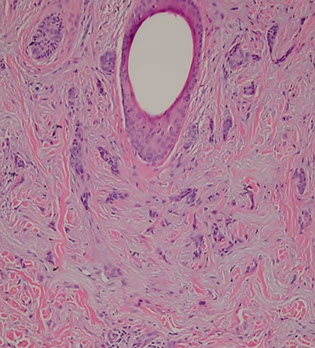

Epidermoid Cyst

- aka Epidermal Inclusion Cyst

Connects through the surface usually with a little hole (punctum) which may have neutro infiltrate if ruptures

- lining looks like surface epithelium but without adnexal structures and can have rete ridge pattern in young cyst that flattens out as pressure increases within the cyst

- can have loose lamellar keratin within the cyst wall